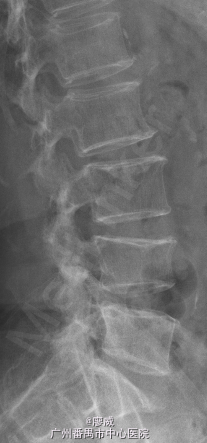

主诉:腰痛2年余,左小腿外侧麻痛半月。 病史:男性患者,52岁。患者2年前在做体力活时出现腰部剧烈疼痛,当时腰部活动受限,在外院门诊诊断为腰肌劳损,给予对症治疗,效果较好。2年来活动后腰部均出现疼痛,反复出现。最近半月以来,患者腰部疼痛时间延长,加重,并伴左小腿外侧麻木,放射痛至足踝处。患者一般情况尚可。

体查:左小腿外侧区域感觉减退;左侧直腿抬高试验50°(+),其余未见明显异常。 辅助检查:三大常规、血生化、肝肾功能均未见明显异常。患者腰椎动力位片正常,其余重要腰椎影像学如下。

目前诊断:腰椎间盘突出症。 处理:入院后完善相关检查,术前给予对症治疗,科里术前讨论决定:拟行手术:椎间孔镜下L4/5椎间盘摘除+椎间孔扩大成形+射频消融术。

讨论:该患者在影像学上看有多个节段的腰椎间盘突出,但最严重的是L4/5,结合患者临床症状及体查,主要也是L4/5。这虽然术后的情况说不定,也许完全缓解,也许还残留其他节段存在的问题。